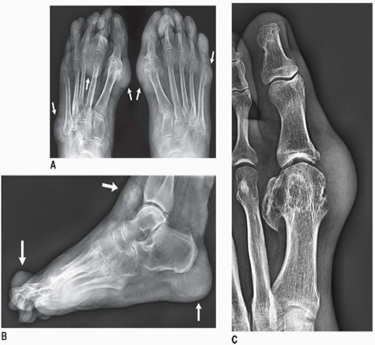

• X-rays may show soft tissue swelling, joint erosion, or crystal deposits (chondrocalcinosis).

• Ultrasound can detect double contour signs and tophi in joints or tendons.

• Advanced imaging like DECT (dual-energy CT) visualizes urate crystals in deeper tissues.